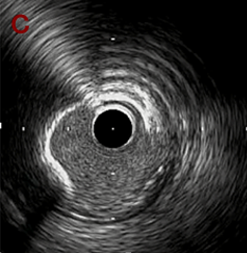

IVUS imaging

IVUSでは8時方向からPD枝がはいいてくる。

PreのIVUSではaの部位のみlipid plaqueを認め削ることでdistal embolismのリスクがあり、そのほかは270度の偏心性石灰化であるがwire biasは良好。

OAS low speedによる引きを赤線の区間行う方針とした。